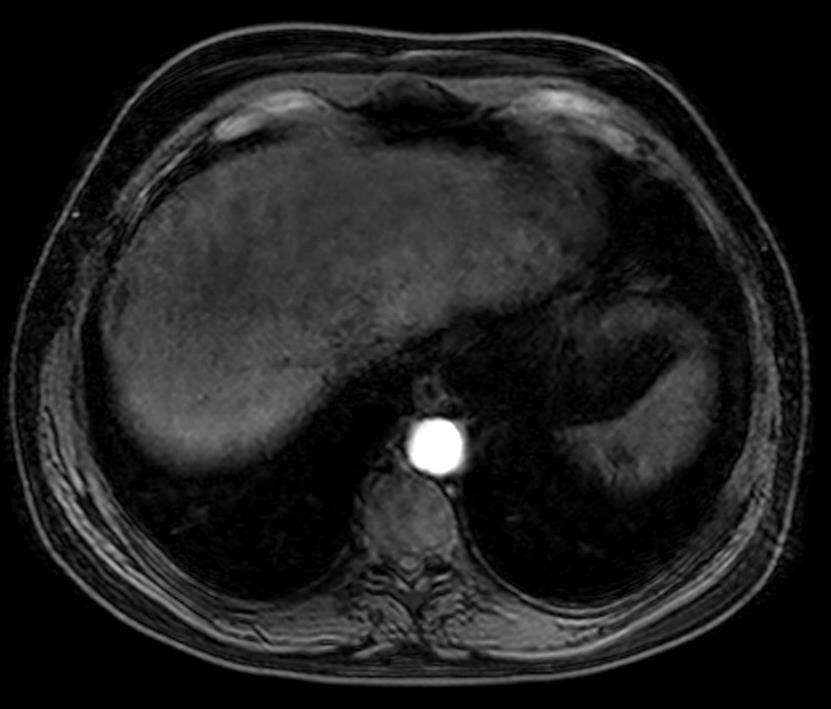

1. 第一个主要的特征:多血管性

在影像上的表现是动脉期增强

增强CT扫描,在动脉后期显示的增强病变应该考虑肝癌的可能性,虽然和造影剂注射速率、造影剂浓度和早期肝癌发现有关。敏感性高,而特异性差。